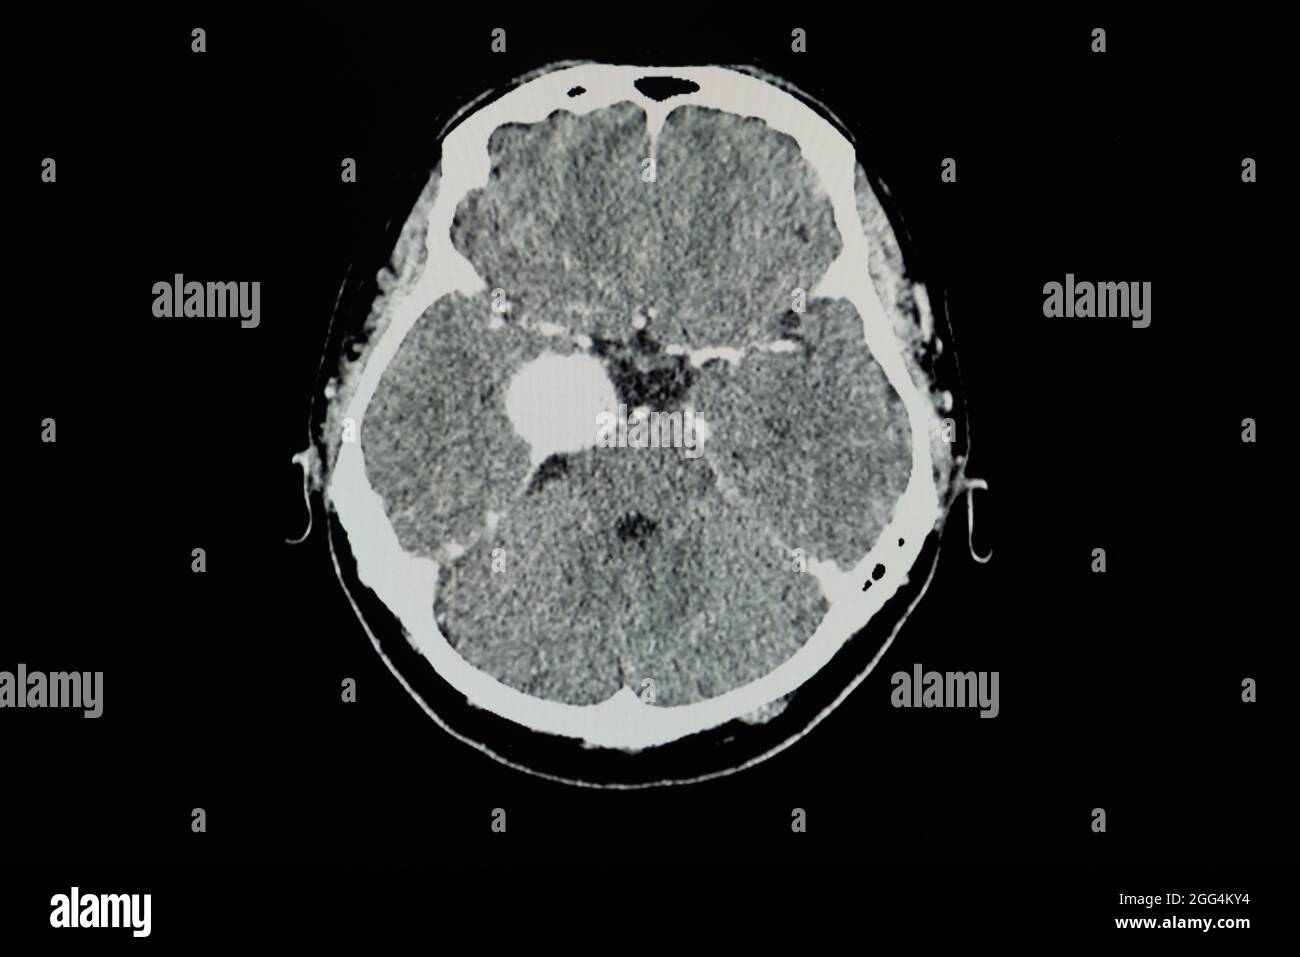

TDM cérébrale avec contraste d'un patient présentant une lésion rehaussant le bord de 3.8 cm au niveau du sinus caverneux droit avec calcification interne, le plus probable ménigiome Banque D'Imageshttps://www.alamyimages.fr/image-license-details/?v=1https://www.alamyimages.fr/tdm-cerebrale-avec-contraste-d-un-patient-presentant-une-lesion-rehaussant-le-bord-de-3-8-cm-au-niveau-du-sinus-caverneux-droit-avec-calcification-interne-le-plus-probable-menigiome-image440197160.html

TDM cérébrale avec contraste d'un patient présentant une lésion rehaussant le bord de 3.8 cm au niveau du sinus caverneux droit avec calcification interne, le plus probable ménigiome Banque D'Imageshttps://www.alamyimages.fr/image-license-details/?v=1https://www.alamyimages.fr/tdm-cerebrale-avec-contraste-d-un-patient-presentant-une-lesion-rehaussant-le-bord-de-3-8-cm-au-niveau-du-sinus-caverneux-droit-avec-calcification-interne-le-plus-probable-menigiome-image440197160.htmlRF2GG4KY4–TDM cérébrale avec contraste d'un patient présentant une lésion rehaussant le bord de 3.8 cm au niveau du sinus caverneux droit avec calcification interne, le plus probable ménigiome